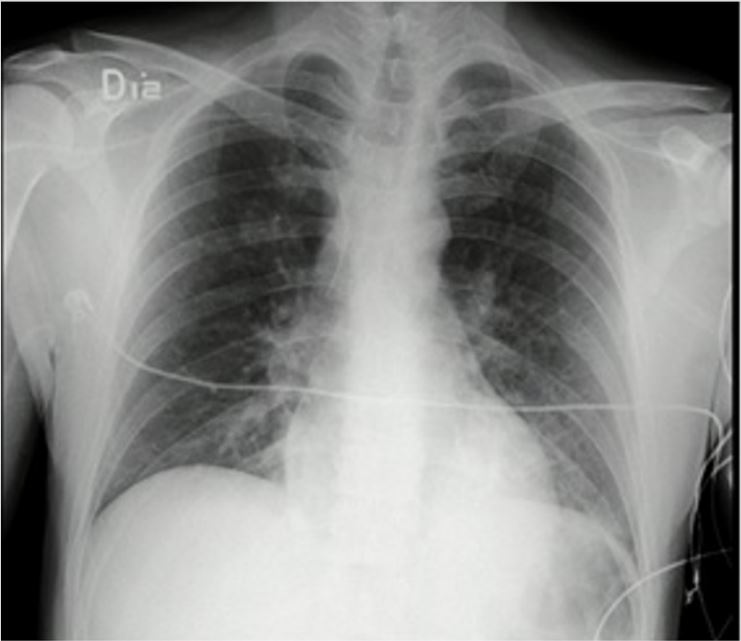

Frente a dichos resultados, se decidió trasladar al paciente a la unidad de cuidados intensivos para continuar el manejo médico con soporte ventilatorio. Por los hallazgos radiológicos de “vidrio esmerilado”, se le tomó la prueba de reacción en cadena de la polimerasa para SARS-CoV-2 en el contexto de pandemia, cuyo reporte fue negativo. Al ser valorado por el servicio de toxicología, este consideró que el cuadro, probablemente, se relacionaba con el consumo de cocaína. Luego de permanecer durante 48 horas con soporte ventilatorio, el paciente logró mejoría clínica, paraclínica y radiológica (figura 2), por lo que fue extubado sin complicaciones, con evolución favorable. Luego de ello se indicó su traslado a la unidad de hospitalización de psiquiatría, de donde egresó siete días después de su ingreso a urgencias.